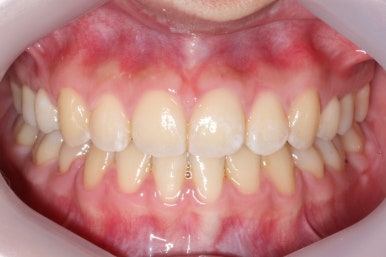

이제 치료가 끝났습니다.

매우 치아가 가지런해졌고, 당연히 덧니는 해소가 되었으며 맞물림도 굉장히 좋아졌습니다.

전후과정을 비교해 보겠습니다.

치아가 매우 가지런해졌고, 덧니도 개선이 되었습니다.

맞물림도 굉장히 좋아졌네요.